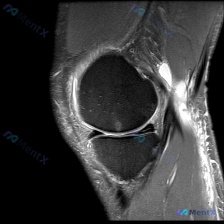

看到这个病例,临床关注点是「膝关节软骨异常」,只拿到了这一张膝关节MRI T1加权轴位图像,整理一下分析思路给大家参考。 一、病例基本影像信息 这是一张股骨远端层面的轴位T1加权图像,先整理一下能看到的信息: 1. 骨结构:股骨内侧髁、外侧髁轮廓清晰,皮质骨连续低信号,骨髓腔内中等信号符合正常表现,...